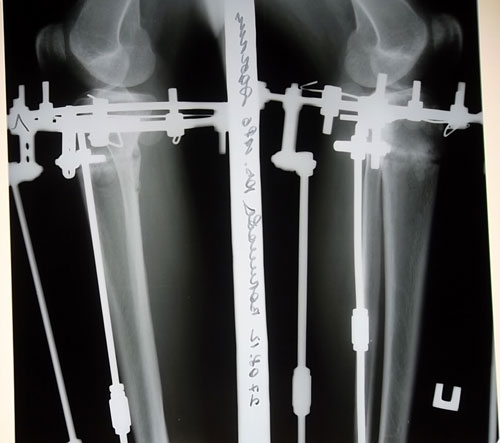

Рентген 2 месяца с момента операции.

Вложения

SAM_3807.JPG

SAM_3805.JPG